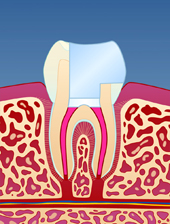

En rotfylt tann er ofte svekket på grunn av store fyllinger og lite gjenværende tannsubstans (fig. I). Som resultat vil en rotfylt tann være mer utsatt for å knekke enn en tann som ikke er rotfylt (fig. II-III). Dersom rotfyllingen blir utsatt for lekkasje over lengre tid, kan bakterier komme til og lage en ny infeksjon i den rotfylte tannen (fig. IV). Der er derfor viktig å kontakte tannlege snarest dersom deler av en rotfylt tann knekker av.

| figur I | | figur II | | figur III | | figur IV |